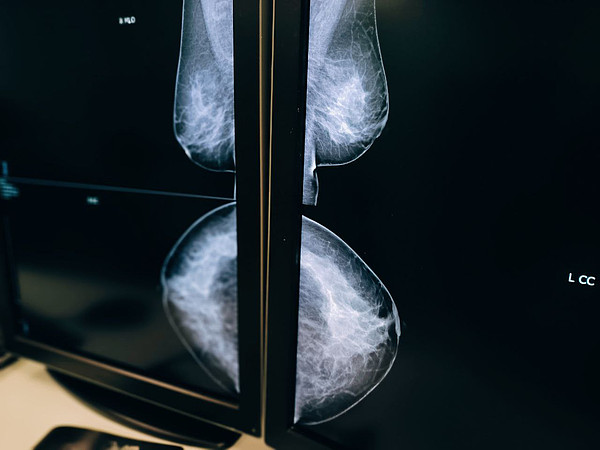

Центр онкологии призывает к ранней диагностике рака молочной железы